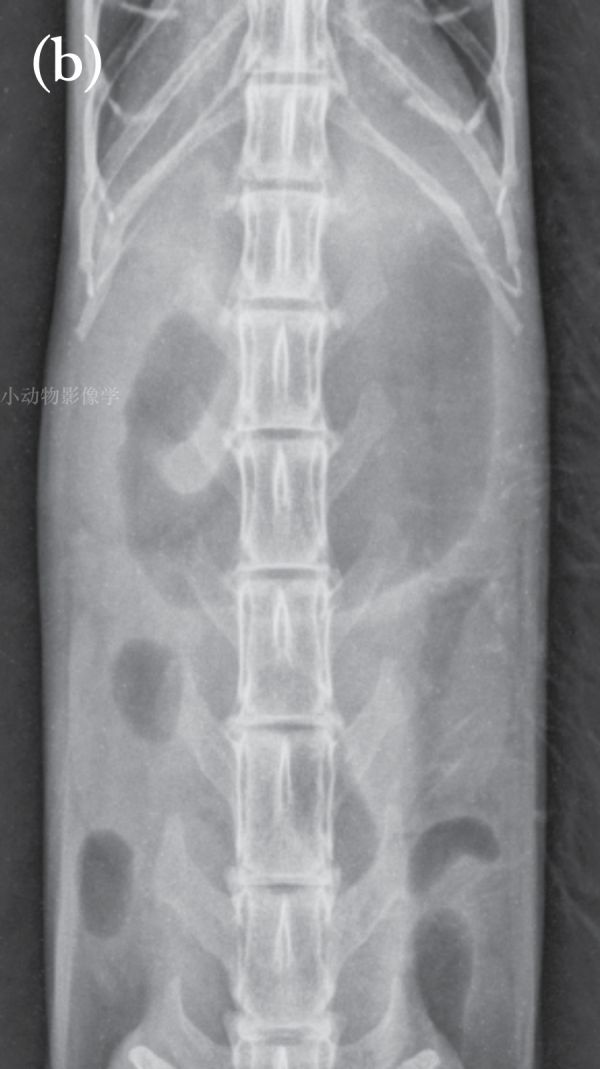

病例1.14岁猫功能性肠梗阻,进食异物后呕吐继发于电解质异常。入院时猫无反应,卧着。(a)左侧位。(b)腹背位。胃是被液体和气体膨胀的在超声检查中,胃(c)和小肠(d)有液体膨胀。(e)胃由于吞食空气,小肠也会膨胀并充满气体,如图所示,这只13岁的猫心脏疾病引起的呼吸窘迫。胸尾部可见胸腔积液(箭头)。